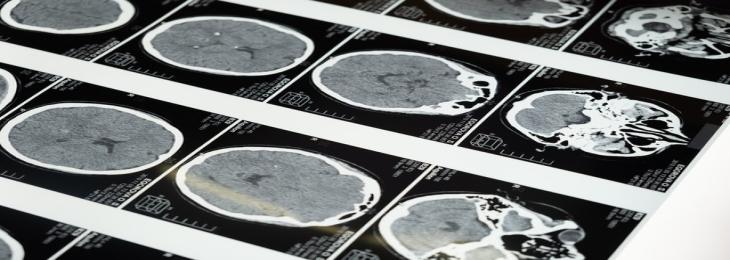

Magnetic resonance imaging (MRI) machine is one of the most important clinical device that is used for evaluation of brain diseases and injuries. However, the high cost and large sizes of this systems limits its use regionally. Now a team of scientists at the University of Hong Kong (HKU) developed a comparatively smaller and low-cost MRI machine that uses a smaller magnetic field without needing a covering, for diagnosis of brain diseases in patients.

MRI technique is used to scan soft tissues in the body. It is specifically effective at diagnosis brain related problems such as injuries, stroke, or tumors. The risk of using this technique are also lesser than other imaging methods such as CT scans or X-rays. However, these MRI machines are of high cost and even the maintenance of these systems is expensive. MRI systems also require high amount of power and bulky radiofrequency and magnetic shielding, which makes the use of this technology expensive in many places, specifically in middle-income countries. However, the new mobile MRI technology uses ultra-low magnetic field with strength of 0.055 T, which eliminates the need for magnetic or radiofrequency shielding, with the use of deep learning algorithms to cut down the inference of electromagnetic signals with the magnets.